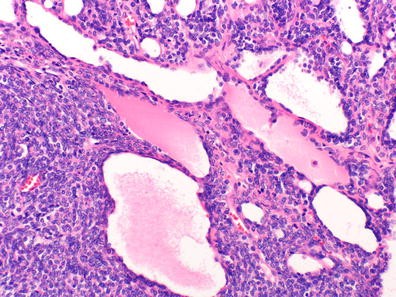

Objective: The aim of this study was to examine the clinicopathological features of succinate dehydrogenase subunit B (SDHB) mutation-related pheochromocytoma/paraganglioma (PCC/PGL).

Method: A total of 15 patients with SDHB-mutation were analyzed genomic DNA, clinical data on family history, catecholamine types, tumor metastasis, patient prognosis, and histology of the tumors. Histologic analyses were performed using the new classification named Grading of adrenal pheochromocytoma and paraganglioma (GAPP) classification that was made based on a nationwide Japanese survey. All tumors were scored from 0 to 10 points, and were also graded according to three differentiation types depending on the total score: well (0–2 points), moderate (3–6) and poor (7–10).